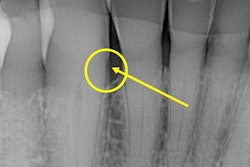

8. Infections inside the tooth (necrotic tooth)

The nerve that lives inside the canal of a tooth is positioned like the carbon in the center of a pencil. It contains blood vessels and nourishing fluids. If it dies or becomes infected, its infection would push out of the tooth at the base of the root (like the carbon point at the writing tip of a pencil). The infection could spread into the surrounding bone causing pain and swelling before moving to other parts of the body.